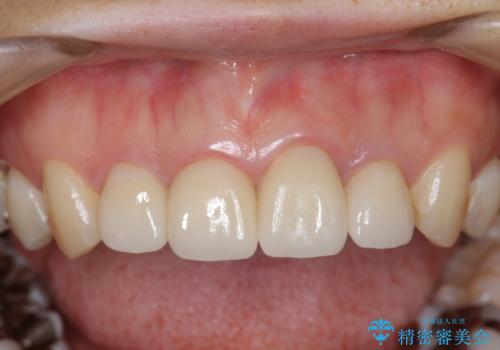

金属のフレームを用いるクラウンは色調が暗くなる傾向にありますが、セラミッククラウンに置き換えたことで自然な明るさ、審美性を取り戻すことができました。

ファイバーコア・セラミッククラウンは金属を用いない審美的な治療法です。